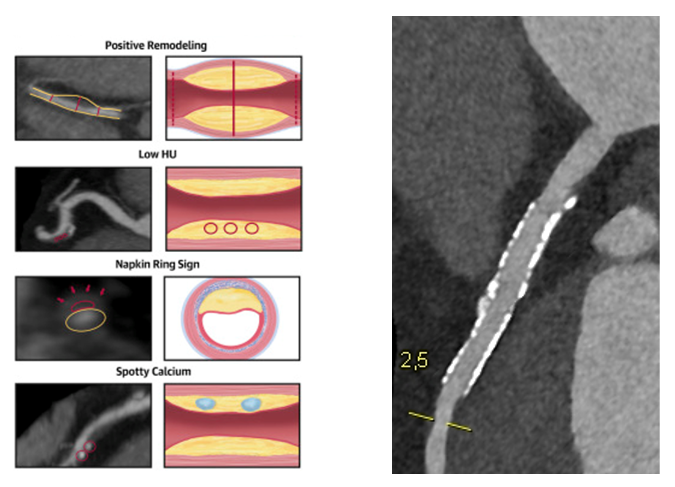

• Beschreibung von kalzifizierten, nicht-kalzifizierten und gemischten Plaques unter Verwendung von Rekonstruktion (Darstellung verschiedener Ebenen: axial, sagittal, koronal und multiplanar; s. Abbildung 1). Erwähnung von „High-Risk-Plaque“-Charakteristika wie positives Remodeling, „low attenuation plaques“, „spotty calcifications“ und „napkin ring sign“ (s. Abbildung 2).

kardiale-ct-hochrisikomerkmale-plaque-charakterisierung-stent-in-proximaler-lad

© Giokoglu

Abb. 2 (links): Hochrisikomerkmale zur genaueren Plaque-Charakterisierung („high-risk-plaques“), Puchner et al., JACC 2014. Abb. 3 (rechts): Frei perfundierter Stent in der proximalen LAD mit Ausschluss einer In-Stent-Restenose mittels Photonen-Counter Technologie (Naeotom Alpha PCCT).